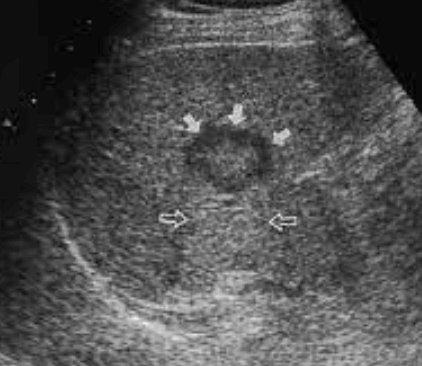

- bull's eys sign (종양 변연에 중심부가 고에코이고 경계부가 저에코인 두꺼운 띠가 보인다)

- cluster sign (종양이 융합하여 분엽모양을 이루어 마치 포도송이 모양을 나타낸다)

전이성 간암의 크기에 따른 종괴형태의 변화

전이성 간암의 크기에 따른 종괴형태의 변화 간세포암과 전이성 간암의 감별진단